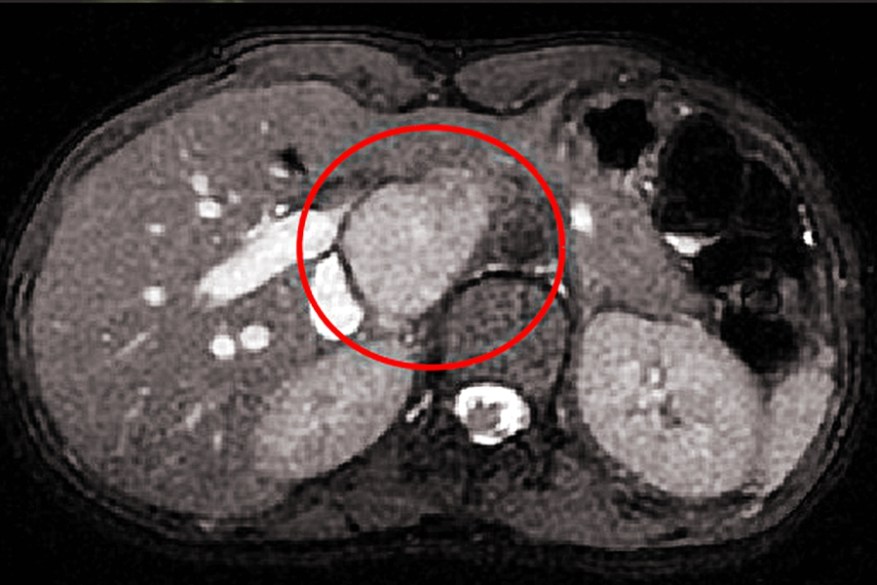

余政展主任從肝臟核磁共振檢查影像確認,腫瘤位於肝臟後面、脊椎旁邊,已經大到擠開腹腔多條大血管,唯一解決方式是切除病灶。但腫瘤被肝臟、胰臟與腎臟血管主動脈,還有下腔大靜脈等大血管緊緊包圍,必須小心沿著大血管手術,稍一閃神幾千毫升的大失血,可能就是病人的生死關頭。